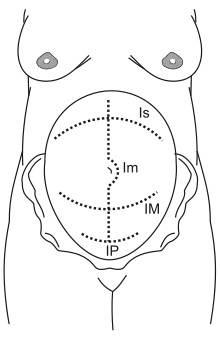

Is: supra-umbilical incision

Im: median incision

IM: Maylard incision

IP: Pfannenstiel incision